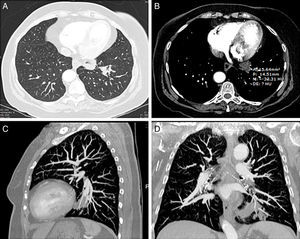

La TC de tórax mostró una consolidación en el lóbulo inferior izquierdo (LII) con áreas de vidrio deslustrado y centro de densidad grasa (fig. 1).

TC de tórax, imágenes axiales con ventana de pulmón (A) y mediastino (B) donde se identifica una consolidación en la base pulmonar izquierda con centro de densidad grasa (−33UH). Las reconstrucciones sagital (C) y coronal (D) demuestran la localización peribronquial de la consolidación del lóbulo inferior izquierdo.